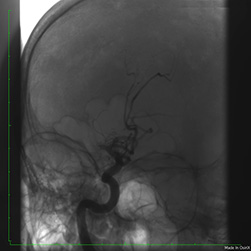

В отделении рентгенхирургических методов диагностики и лечения выполнена ангиография правой внутренней сонной артерии, на которой выявлена тромботическая окклюзия (закупорка просвета) правой среднемозговой артерии в М1 сегменте (рис. 1).

![]() рис 1. Тромботическая окклюзия правой среднемозговой артерии в М1 сегменте |